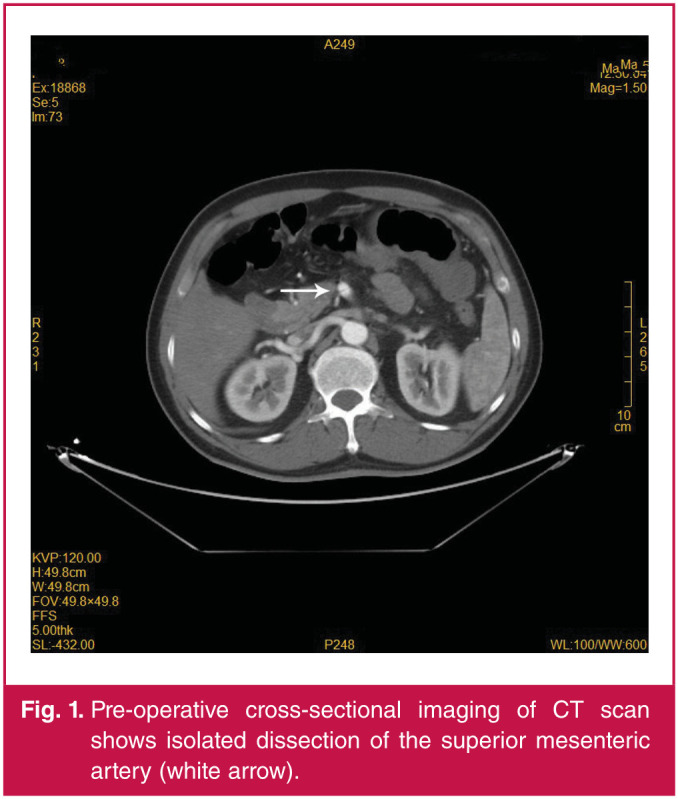

Spontaneous isolated superior mesenteric arterial dissection with coeliac axis stenosis is rare but serious. We report a case of a 54-year-old male with coeliac axis stenosis who presented with acute superior mesenteric arterial dissection, which caused thrombosis of the branches. This is the first report of the full course of treatment using endovascular repair and laparoscopic surgery to deal with spontaneous isolated superior mesenteric arterial dissection combined with coeliac axis stenosis. This approach has been shown to be safe and effective for yielding short-term results.